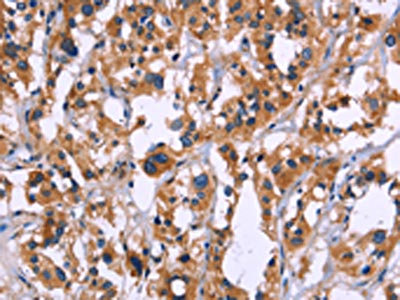

The image on the left is immunohistochemistry of paraffin-embedded Human thyroid cancer tissue using CSB-PA708659(ZEB2 Antibody) at dilution 1/60, on the right is treated with fusion protein. (Original magnification: ×200)

The image on the left is immunohistochemistry of paraffin-embedded Human breast cancer tissue using CSB-PA708659(ZEB2 Antibody) at dilution 1/60, on the right is treated with fusion protein. (Original magnification: ×200)